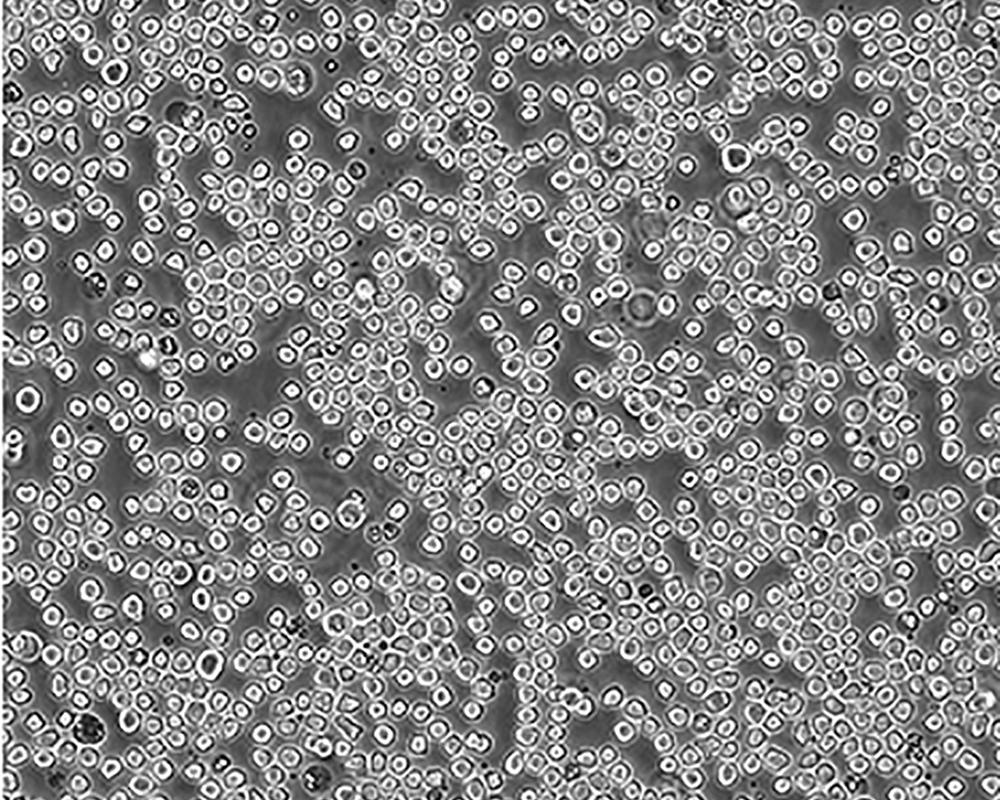

生長(zhǎng)特性 suspension

形態(tài)特征 monocyte

細(xì)胞描述 該細(xì)胞是由NilssonK實(shí)驗(yàn)室于1974年從一名37歲的患有惡性組織細(xì)胞性淋巴瘤的白人男性的胸水中分離建立的。1979年來(lái)的研究顯示該細(xì)胞在人混合淋巴細(xì)胞培養(yǎng)物上清、佛波酯、VitD3、γ-IFN、TNF和維A酸的誘導(dǎo)下可以向終末單核細(xì)胞分化。該細(xì)胞不合成免疫球蛋白,EBV陰性;可產(chǎn)生溶菌酶、β-2-微球蛋白,受PMA刺激后可產(chǎn)生TNF-α;表達(dá)C3R;可作轉(zhuǎn)染宿主;表達(dá)Fas,對(duì)TNF和抗Fas的抗體敏感。